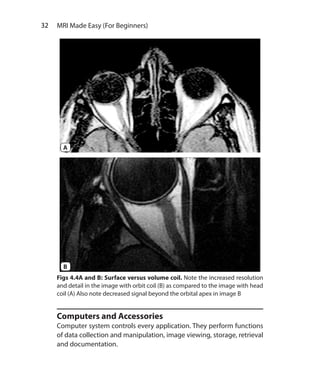

Computers and Accessories

Computer system controls every application. They perform functions

of data collection and manipulation, image viewing, storage, retrieval

and documentation.

Figs 4.4A and B: Surface versus volume coil. Note the increased resolution

and detail in the image with orbit coil (B) as compared to the image with head

coil (A) Also note decreased signal beyond the orbital apex in image B